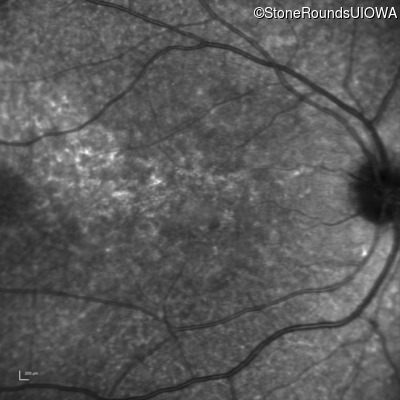

Age at visit: 30 years

This 30 year old man first noticed poor vision in dim light when he was five years old. His visual acuity began to fall in his early 20's.